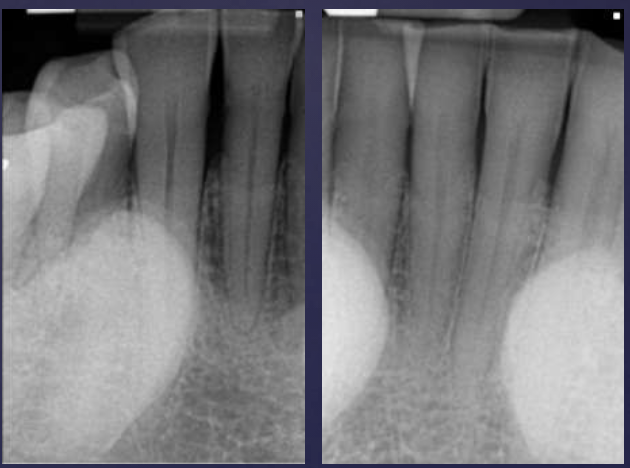

describe the ameloblastoma in this radiograph

multilocular w/ coarse septae

thinning of inferior mand border

displacement of teeth + IAN